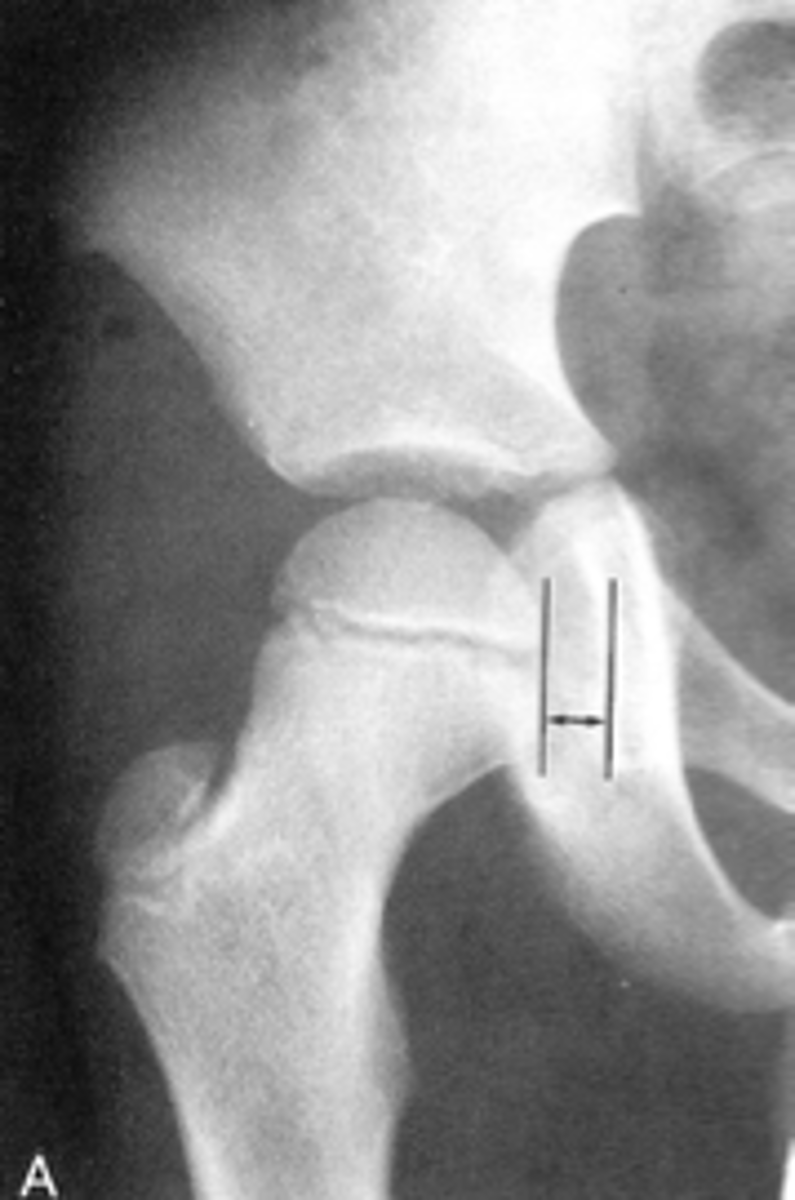

Kohler's teardrop distance

ID measurement line

<p>ID measurement line</p>

36

New cards

- AP pelvis

- AP hip

What views are needed to see Kohler's teardrop distance?

<p>What views are needed to see Kohler's teardrop distance?</p>

37

- Medial margin of femoral head

- Lateral border of teardrop

Kohler's teardrop distance landmarks

<p>Kohler's teardrop distance landmarks</p>

38

6-11 mm

Normal Kohler's teardrop distance measurement

<p>Normal Kohler's teardrop distance measurement</p>

39

2 mm

The normal Kohler's teardrop distance is 6-11 mm, and there should be no greater than a _____ difference when comparing to the contralateral side

<p>The normal Kohler's teardrop distance is 6-11 mm, and there should be no greater than a _____ difference when comparing to the contralateral side</p>